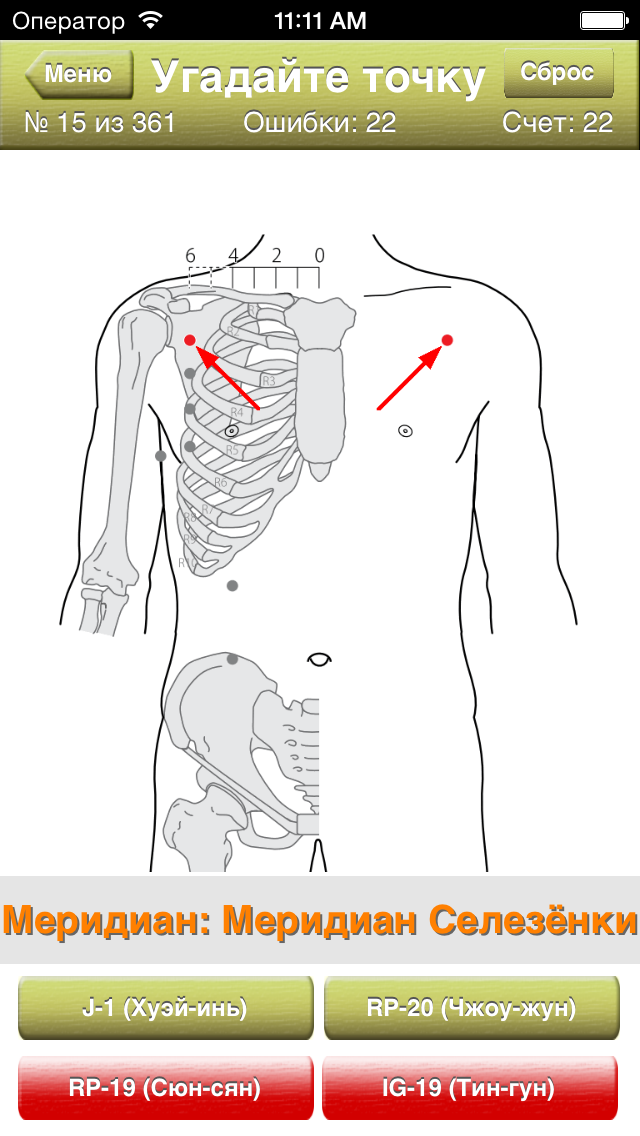

Скриншоты